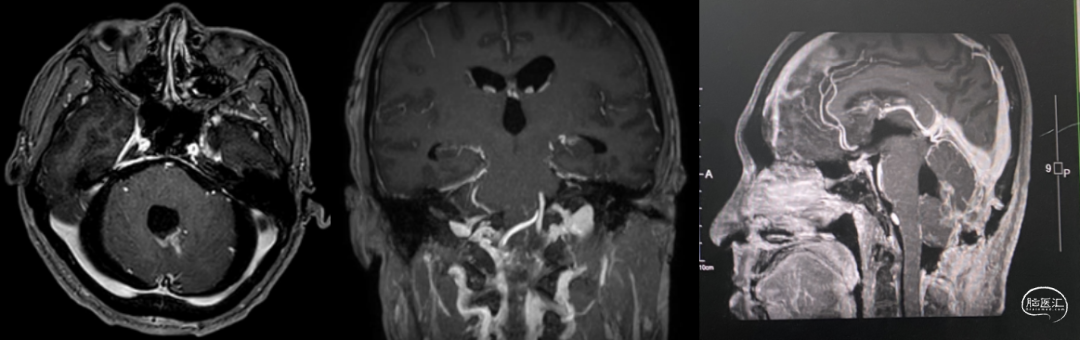

术前MRI:T2显示瘤周大量流空信号影,Flair显示左侧瘤周水肿边界欠清。

T1增强显示肿瘤血供非常丰富,有粗大引流静脉向窦汇及直窦引流。

DSA:显示肿瘤主要由PICA及SCA分支供血,单支向上向窦汇引流。

术后2周MRI:肿瘤全切。